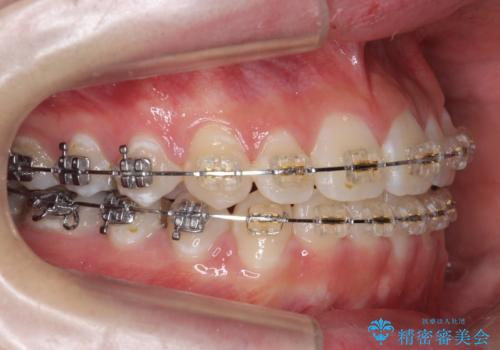

下の小臼歯を抜歯しましたが、その代わり下の親知らずを残して咬ませたので、歯の数は変わっていません。

ただし、左下の親知らずを残すには厚みのある歯ぐきを処置しています。(ディスタルウェッジ)

左上奥歯は、矯正後セラミックインレー修復を行なっています。

親知らずが歯ぐきに埋まっていると不潔になり、炎症を繰り返すため残しておくことが難しい場合が多いです。

今回は左下の小臼歯を1本抜歯してるのと、手術を行なって親知らずを顎に収めることができました。